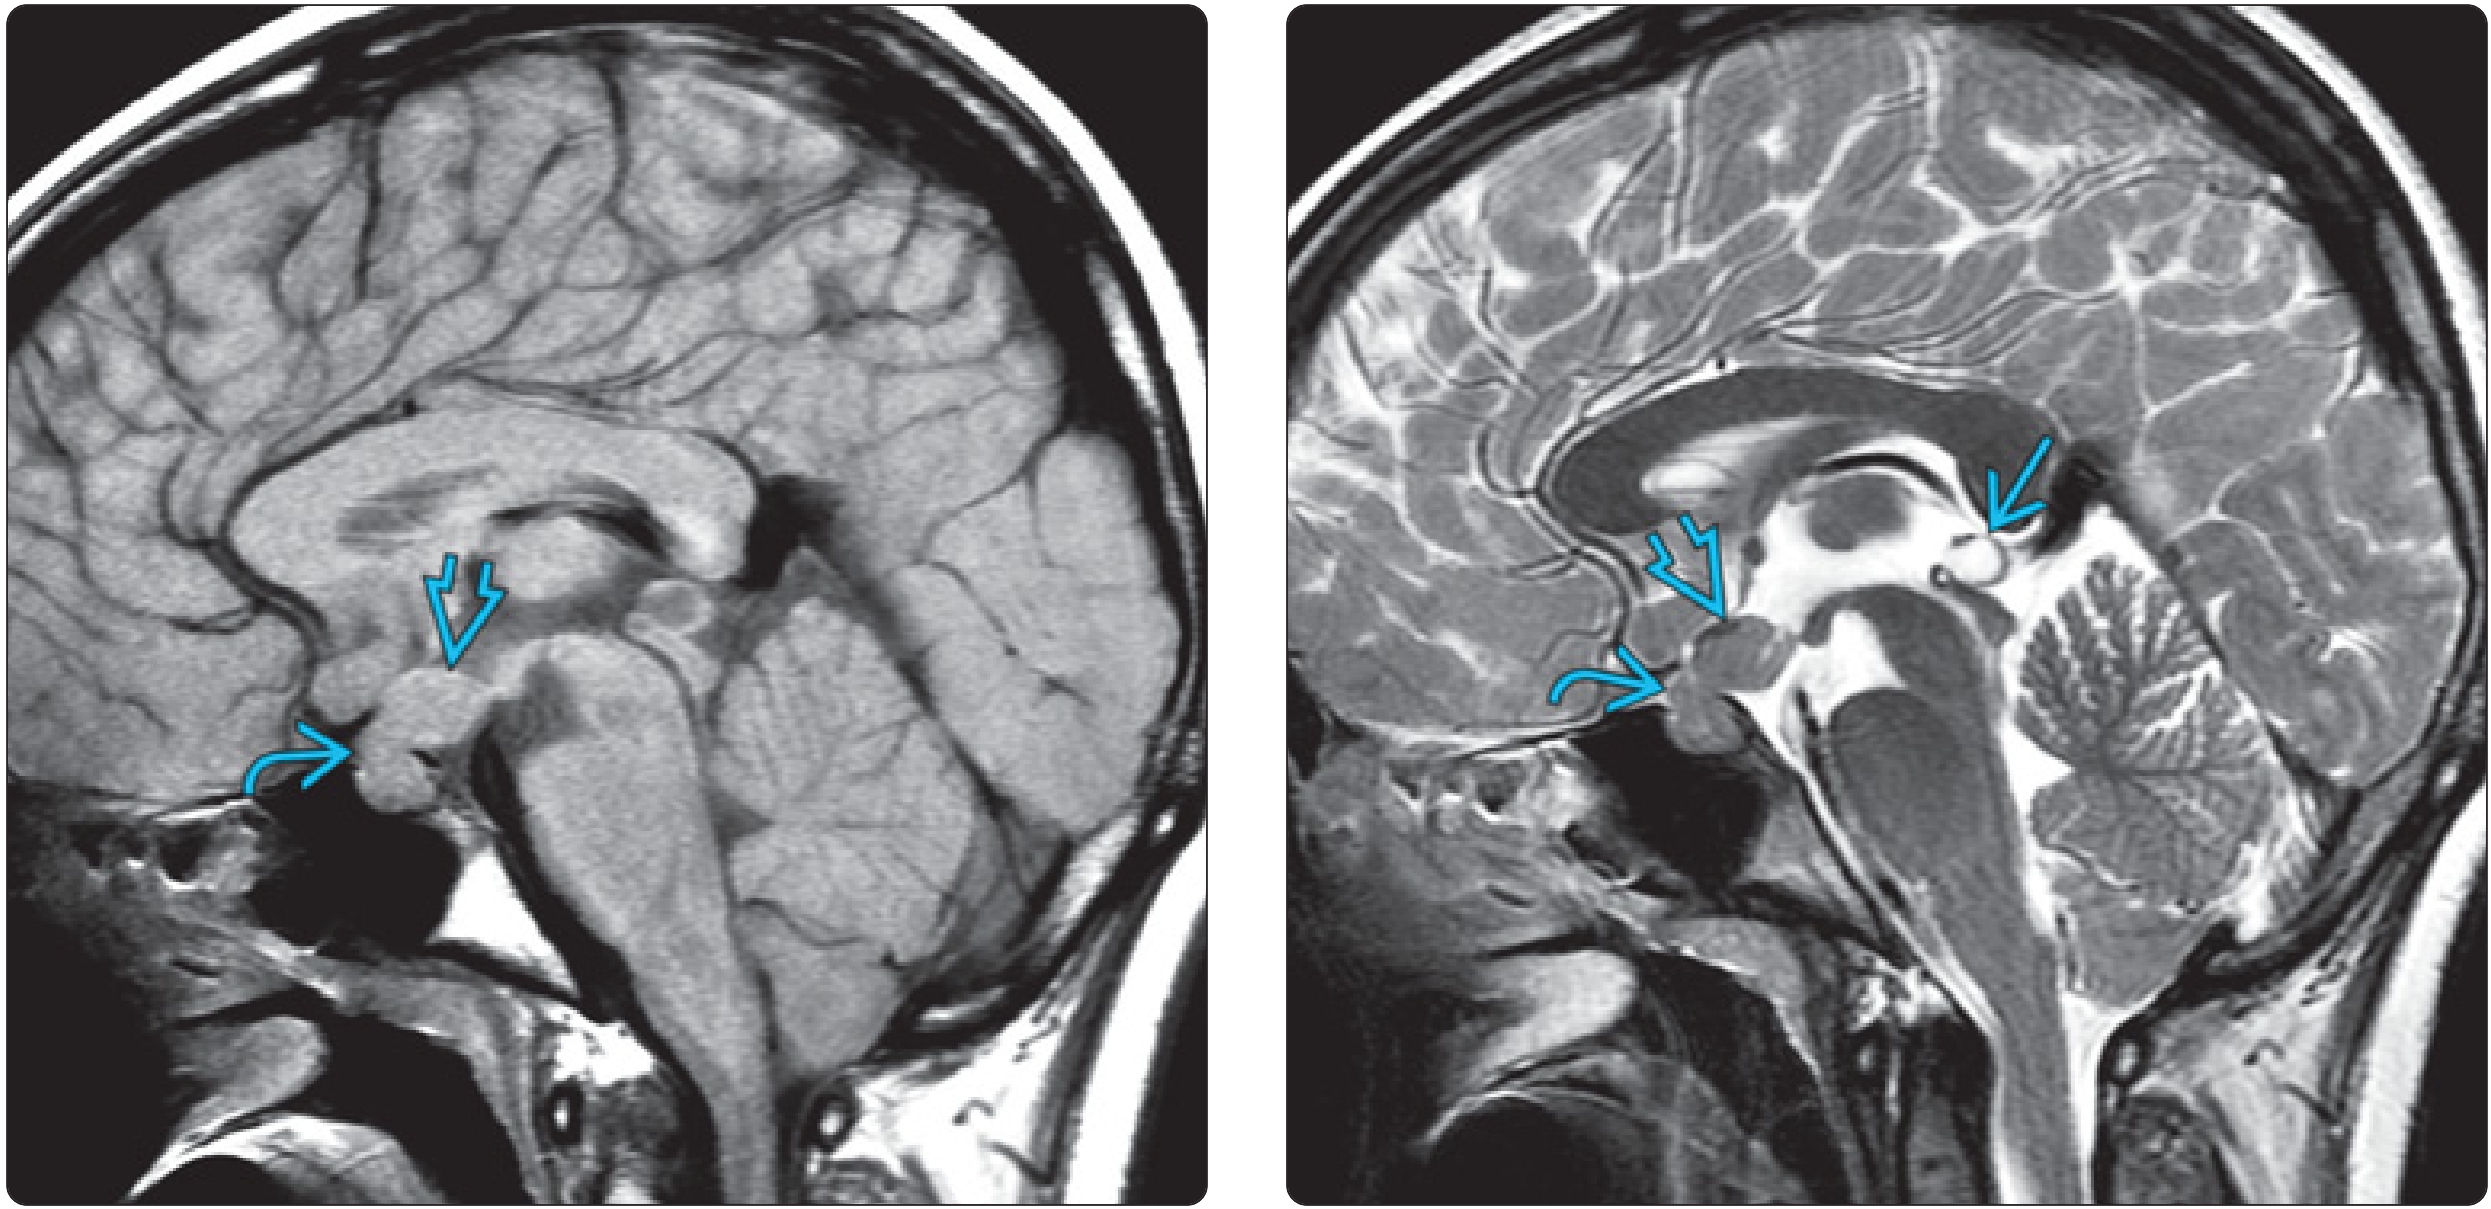

(左)14岁尿崩症女童矢状体 T1Wl显示垂体后叶缺失亮点啊。”与皮质等强度的细小肿块增厚了下颌骨柄,向上延伸至下丘脑和第3脑室。(右)同一患者的矢状T2WI显示垂体柄和下丘脑/下三脑室与灰质等信号。注意良性出现的松果体囊肿

(左)一名患有尿崩症的14岁女孩的矢状T1Wl显示垂体后叶“亮点”缺失。一个与皮质紧密相连的分叶状肿块使漏斗状茎Z向上延伸到下丘脑和第三脑室E>,(右)同一患者的矢状T2Wl显示,垂体茎和下丘脑/下第三脑室的肿块仍呈灰色,注意良性外观松果体囊肿